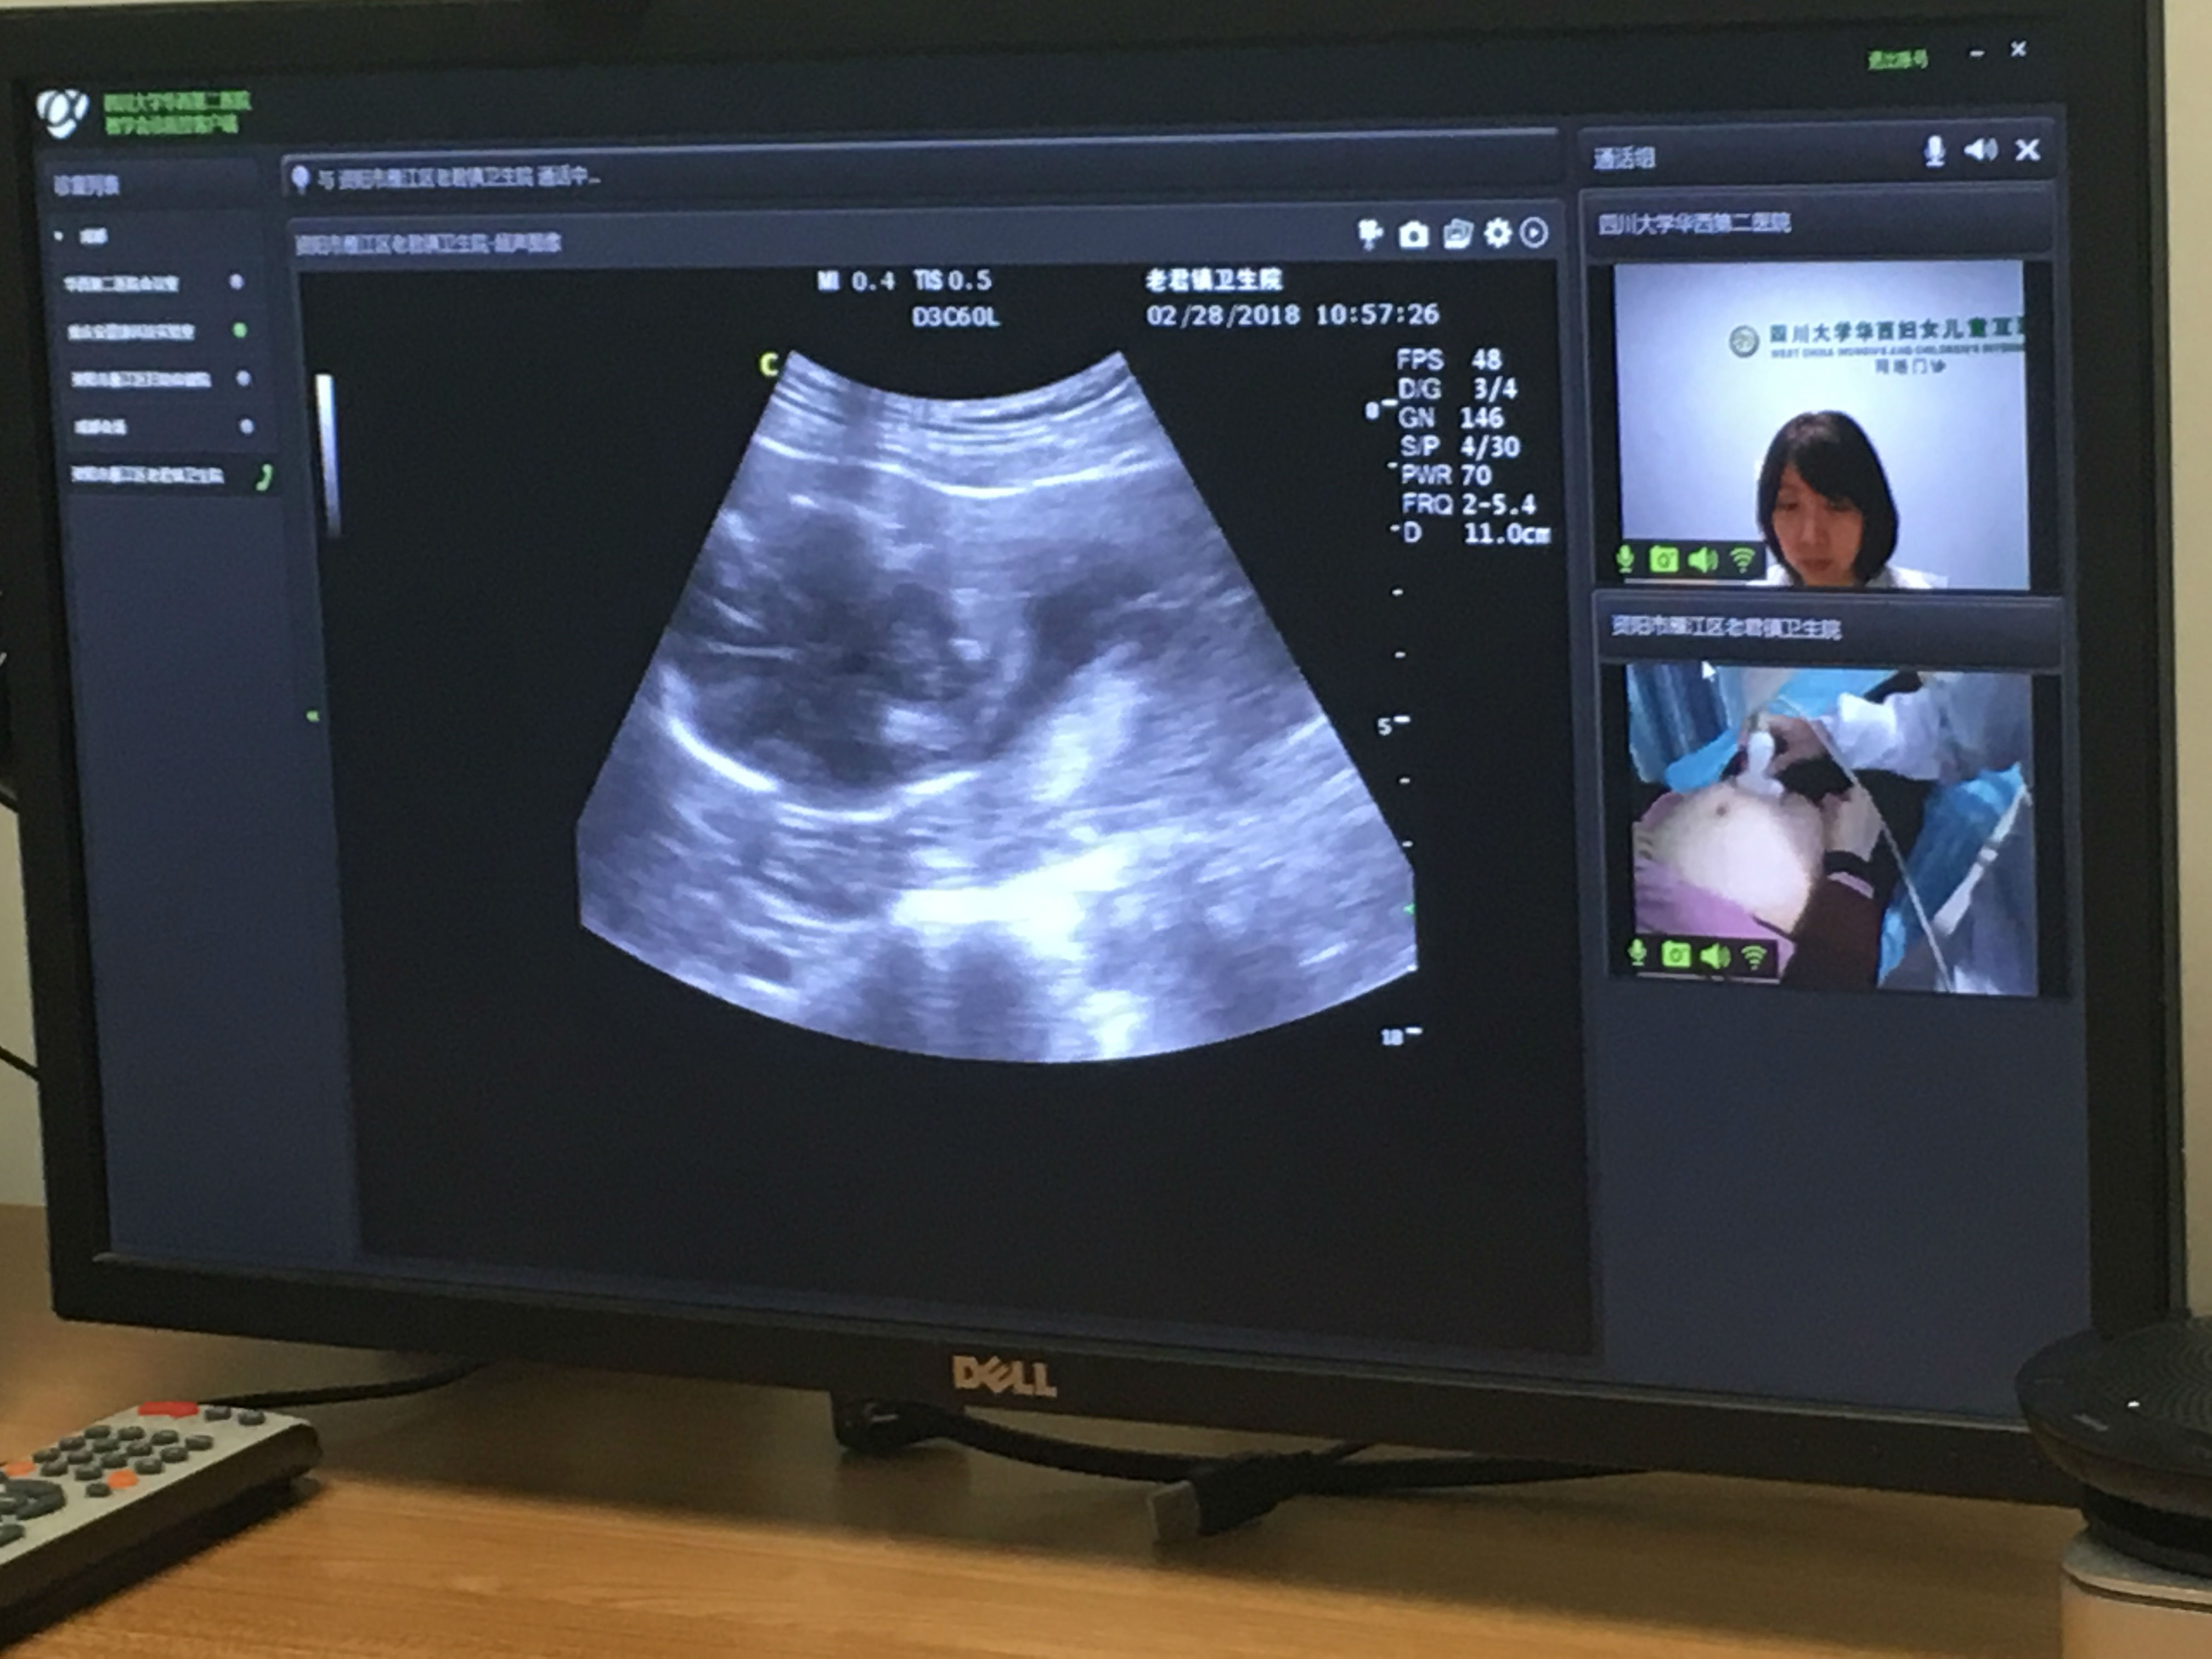

2月28日上午,我院超声科医生王静欣同资阳市老君镇乡镇卫生院罗主任利用我院医联体远程超声会诊系统进行了远程会诊,我院超声科医生王静欣对当地医生进行了实时的业务指导。

本次远程超声会诊是由资阳市卫计委为专题报道远程医疗情况为契机,老君镇乡镇卫生院作为我院医联体成员资阳市妇幼保健院三级妇幼保健网帮扶对象,成功与我院进行了实时交流,充分体现我院优质医疗资源下沉到基层的措施。

资阳市电视台对本次会诊进行了全程录制。(供稿:宁静 摄影:宁静)